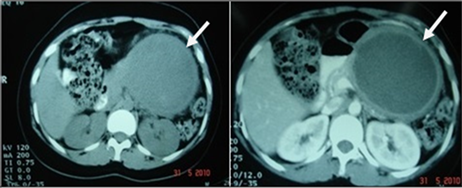

Figure 1. Class CE2 Hydatid cyst in liver in a 60 yr male patient with history of right hypochondriac pain. Plain and CECT abdomen showed multivesicular cystic lesion with attenuation of mother cyst is higher than that of daughter cysts and thin high attenuation peripheral rim on plain CT with no enhancement on postcontrast.

Figure 2. Multiple intraperitoneal Hydatid cysts in mesentery and liver in a 22 yr male patient with right hypochondriac and epigastric pain with early satity. Plain and CECT abdomen showed Class CE2 cyst in liver, Class CE1 and CE3 cysts in mesentery. Most of the cysts show hyperdense peripheral rim on plain CT. Class CE3 cyst is deformed with floating membranes within.

CT: Type II HCs are sub classified into 3 types based on the age, number, and arrangement of the daughter cysts. Type IIA lesions contain round daughter cysts arranged at the periphery. The average CT attenuation of the mother cyst is higher than that of daughter cysts [Figure 1].

Type IIB lesions contain larger, irregularly shaped daughter cysts occupy the almost entire volume of mother cyst. The high attenuation fluid within the mother cyst that surround the daughter cysts looks like septa, creating a “rosette appearance’’ [Figure 2(a) and Figure 2(b), Figure 10, Figure 13, Figure 16].